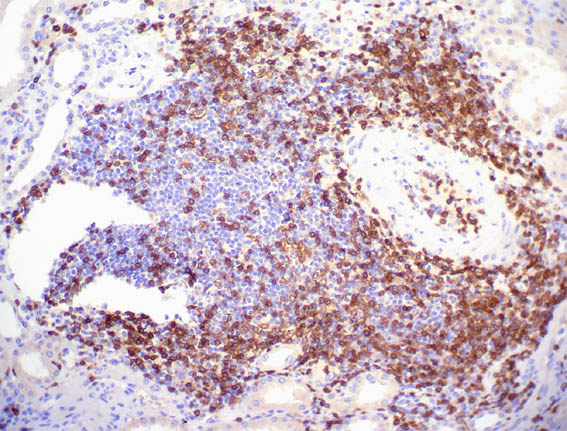

Figure 11. Immunohistochemistry for CD30, X400.